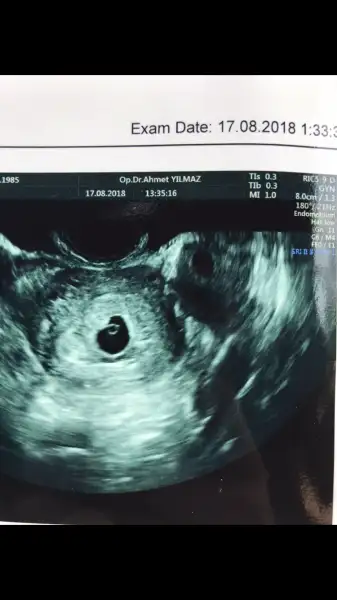

Kızlar doktordan çıktım. Çok şükür bebek oluşumu gözleniyor yolk var dedi.Ben asla kürtaj demem dedi. Yamuk falan da değil gayet düzgün normal bir kese deri.Dünkü ultrasonu gösterdim. Bişey Diyemem ama içinde oluşum var boş gebelik değil kesinlikle bekliyoruz dedi bayramda burdayım birşey olursa ara dedi cts günü kontrole gel kalp atışlarına bakalım geç döllenme olabilir çok küçük daha dedi. Düşerse de kendi düşsün 1mküplük su alanı büyük bir düşük olmaz kürtajlık bir durum değil dedi. Allahım sana binlerce kez şükürler olsun. Sizlerden de Allah razı olsun merak edip önem verip cevap yazmışsınız Allah sizinde gönlünüze göre versin. Yinede cts kalp atışı için endişeliyim ama beklediğim için çoooook mutluyum Allahım